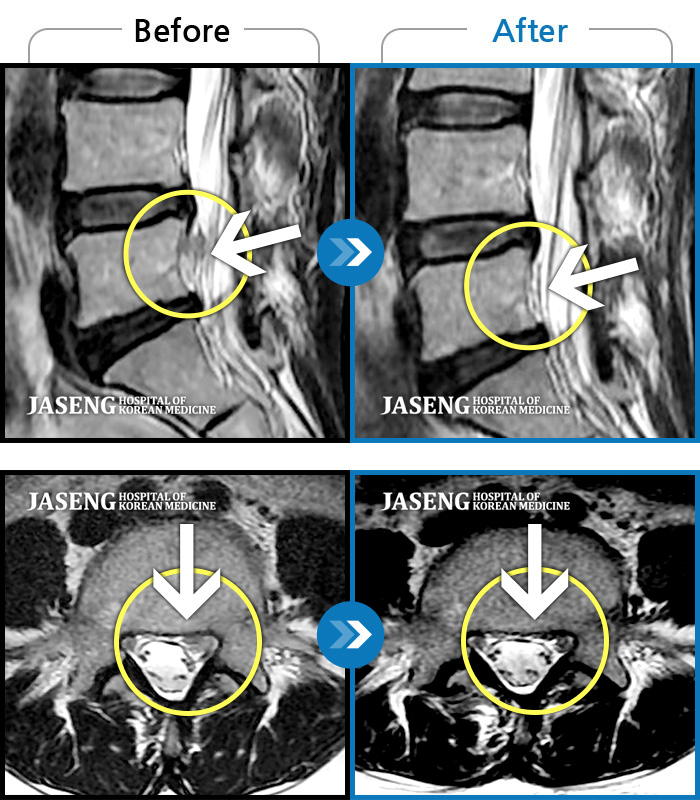

허리디스크

부천 · 신동재 원장

의자 위를 여러 번 올라갔다 내려갔다 반복한 뒤 극심한 하요부 통증 및 좌측 하지부 저림

촬영시기

2024.06.22 ~ 2024.11.19

2024.11.29

조회수 473